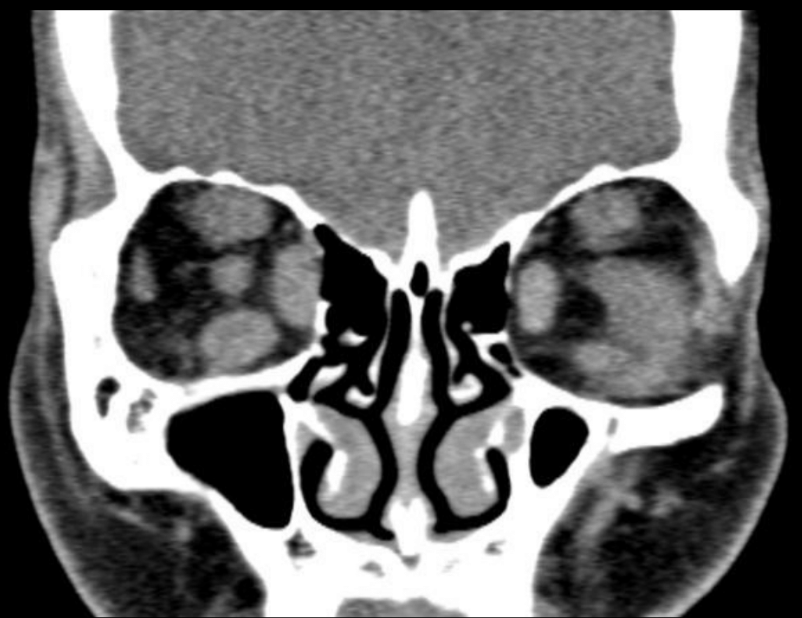

¿Qué esperamos encontrar en estudio de imagen para enfermedad de Graves?

Agrandamiento bilateral de los músculos extraoculares y diametro disminuido en el nervio óptico por alargamiento

Q

Enfermedad de Graves

Diagnóstico

Graves